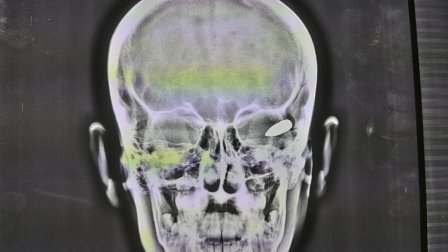

بالصور.. انقاذ طفل أصيب برصاصة طائشة اخترقت عمق دماغه

، الثلاثاء، عن نجاح فريق طبي من إخراج رصاصة طائشة أصابت طفل في العاشرة من عمره استققرت بعمق دماغه وتسببت له بشلل وفقدان بالوعي، مشيرا الى أن العملية كانت خطرة ومعقدة.

أعلن مدير

وقال مدير مستشفى ورئيس الفريق الطبي الدكتور

سمير حميد

الدلفي، في حديث لـ

السومرية نيوز

، إنه "وبحسب ذوي الطفل فأنه أصيب برصاصة أثناء اللعب في رأسه قرب منزله بمنطقة الحسينية ببغداد ما تسبب له بشلل بالحال ونقلوه على إثرها إلى طوارئ

مستشفى ضاري الفياض

إلا أن المستشفى طلبت منهم إحالته إلى الجملة العصبية لصعوبة حالته".

وأضاف الدلفي أن "المستشفى استقبلت الطفل ذو العشرة أعوام وهو يعاني من نزف بالدماغ وشلل بالاطراف وضعف بالتركيز وفقدان بالوعي".

وأوضح أنه "بعد إجراء الفحوصات السريرية والإشعاعية تبين أن الرصاصة اخترقت عمق الدماغ ماتسببت له بشلل".

وتابع أنه تم "إجراء عملية معقدة لإخراج الرصاصة وتكللت بالنجاح"، مشيرا إلى أن "العملية أجريت بمساعدة فريق طبي مكون من د. مكرم

نور الدين

و د. اوفى اكثم و اخصائي التخدير د. احمد علي محروس ومساعد مخدر

علاء حسين

والممرضة فردوس ناظم والفيزياوي احمد علي".

ودعا الدلفي "الجهات المسؤولة الى اتخاذ أقصى العقوبات بحق مطلقي العيارات النارية لمنع تكرار مثل هذه الإصابات التي تسببت بكوارث راح ضحيتها العديد من المواطنين الأبرياء ".